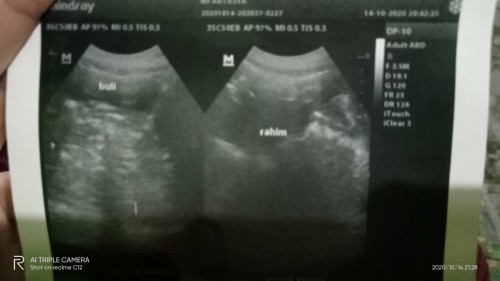

Bundaa bundaa saya mau cerita nih kan kan saya pernah usg waktu usia kandungan 7week tapi kata dokter di rahimnya masih belum ada apa apa... Terus katanya gini â2minggu lagi kembali ya bu kalau 2minggu lagi di usg belum kelihatan apa apa di kurret ajaâ katanya juga bisa jadi hamil b.o / di luar kandungan... Tanda tanda hamil diluar kandungan itu apa ya bun? Dan apakah bunda pernah usg 7week belum kelihatan apa apa bahkan kantungnya saja belum kelihatan... Saya takut kenapa kenapa bunda dokternya kemren bikin down juga... Penantian 2th...#seriusnanya #bantusharing